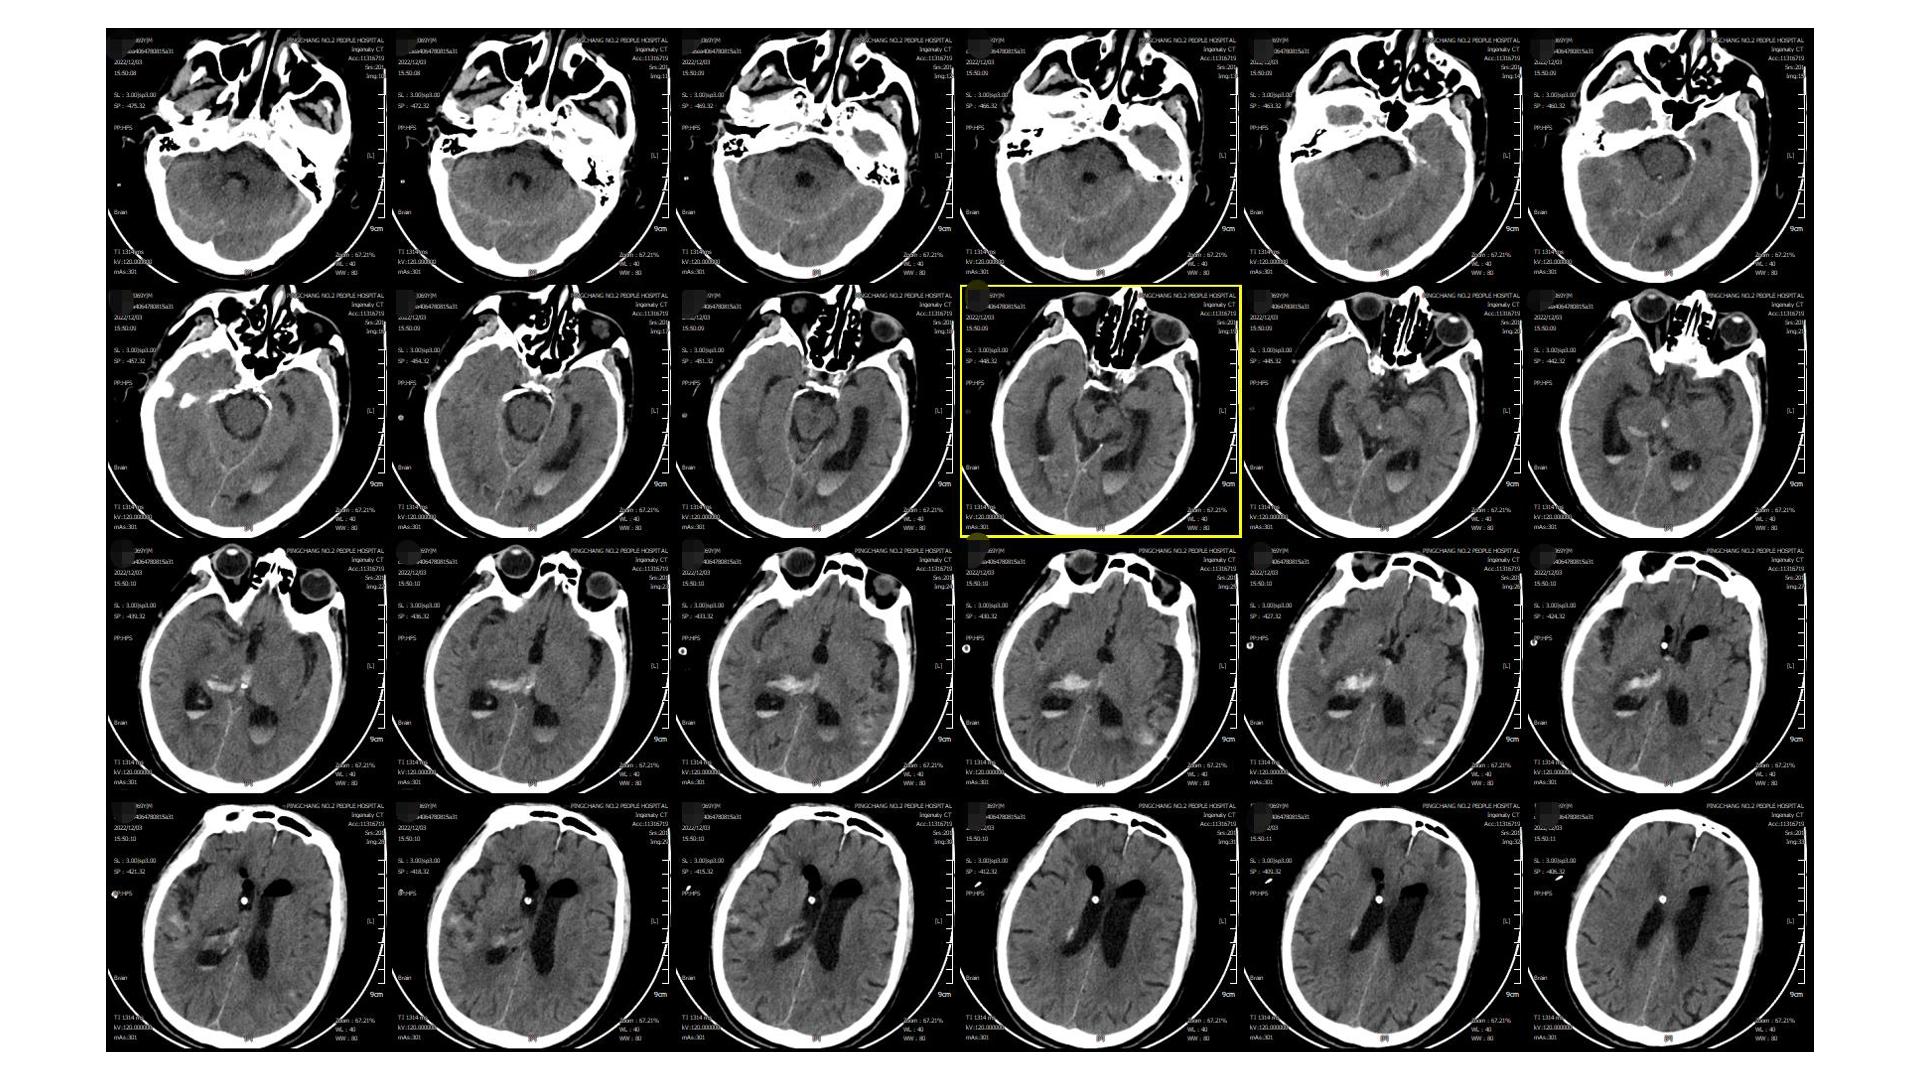

2022.12.12

2022.12.12,血肿基本干净,留取脑脊液送检无颅内感染征象,予以拔除EVD引流管,腰穿释放蛛网膜下腔血性脑脊液